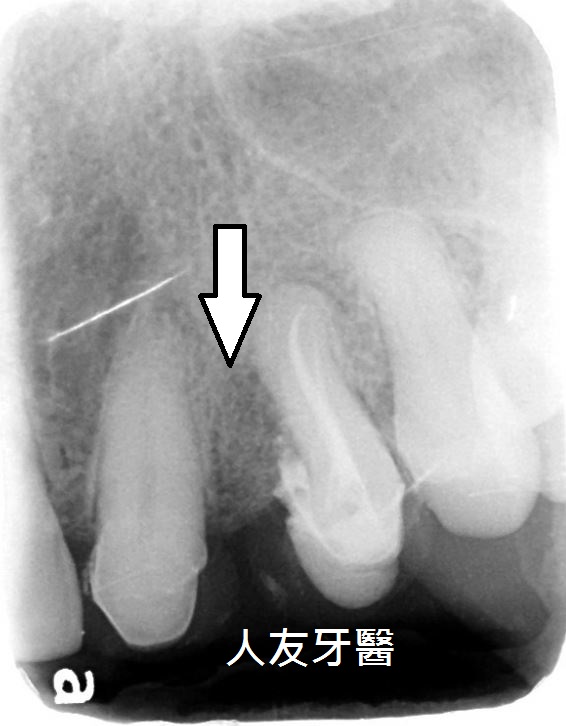

而左側門牙根尖有一個病變,醫師透過根管治療的方式把牙根深層的細菌清除乾淨,放入柱心補強,最後再搭配牙套保護.

患者左上犬齒與第一小臼齒中間的縫隙很容易塞食物,牙根裸露也讓舊式牙套包覆性變得很不好。(上下圖箭頭處)

經醫師評估後,建議患者先拆除舊式金屬牙套,並利用數位掃描並設計美容樹脂牙套先測試,期間治療牙周病,及小臼齒根管治療,牙周病控制下來後並進行人工骨粉填補地基掏空的部分。(下方兩圖)

牙齒進行根管治療時,醫師會先清除牙髓及牙根管中的發炎組織,清除完並沖洗乾淨後再將牙根管填補進牙齒中,如此一來可以保留牙根,可穩固牙根,根 管治療完成後會置放一根柱心強化(下方圖)。

後續進行電腦掃描利用數位設計製作全鋯牙冠贗復,既美觀又自然。(下圖箭頭處)強化及恢復牙齒原來的功能及型態。